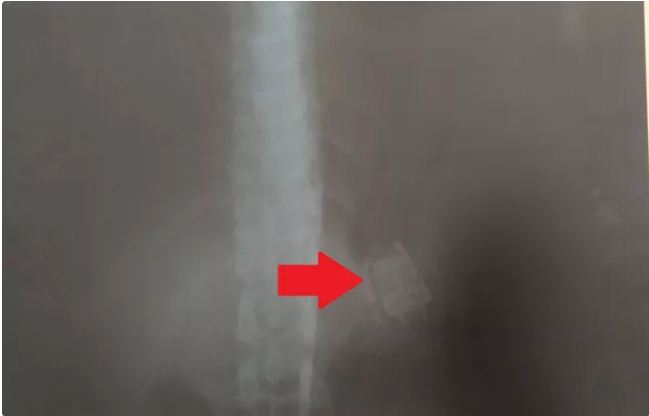

Sorocaba - Agentes penitenciários do Centro de Detenção Provisória (CDP) de Capela do Alto(SP) detectaram um celular alojado no estômago de um detento por meio de scanner corporal. O apenado foi encaminhado para o pronto-atendimento de Capela do Alto e passará por cirurgia para a retirada do objeto.